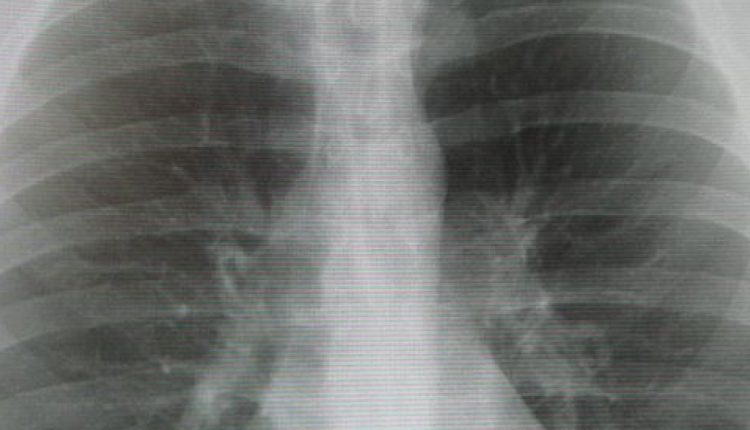

Флюорограмма может быть нормальной — у здорового человека, который раньше не болел никакими заболеваниями легких. Норма флюорографии — это прозрачные легочные поля без каких-либо затемнений.

Бывает флюорограмма патологическая — когда обнаруживаются изменения, свидетельствующие о перенесенной или имеющейся болезни: